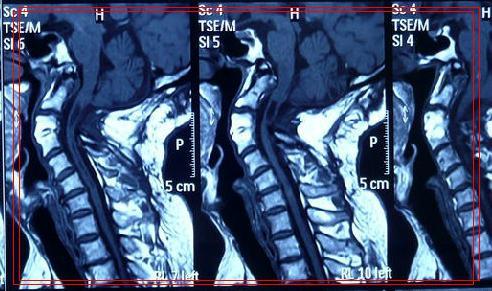

术后影像学